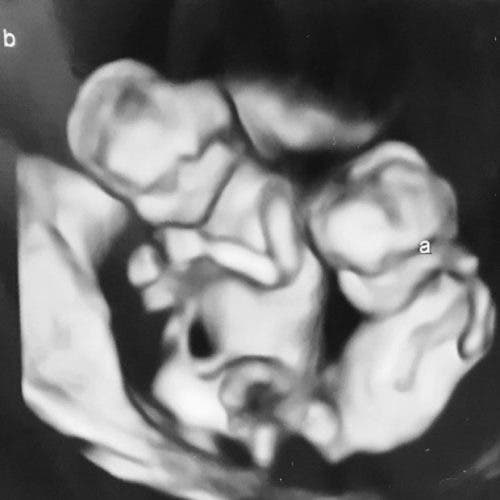

A las 07:55 pm nació la pequeña Lyric y tres minutos después su gemela Cali. Las pequeñas pesaban menos de 500 gramos cada una y medían sólo 26,5 centímetros. La madre estaba contenta de que a pesar de lo prematuro del nacimiento, había oído llorar a las dos bebés durante el parto y eso era un buen síntoma pero el 17 de julio la situación se complicó para Cali.

La bebé sufrió una hemorragia cerebral severa de cuarto grado y sus signos vitales eran cada vez menores. El doctor informó a los padres que incluso si la mantenían conectada con el ventilador la pequeña estaría sufriendo, así que tomaron la decisión más difícil de sus vidas.

Por otro lado, Lyric se aferra a la vida. La bebé sufrió una hemorragia de primer grado y la operaron por un intestino perforado. La niña también tiene un neumotórax, una bolsa de aire en los pulmones, por lo que le insertaron otro tubo allí hace una semana.